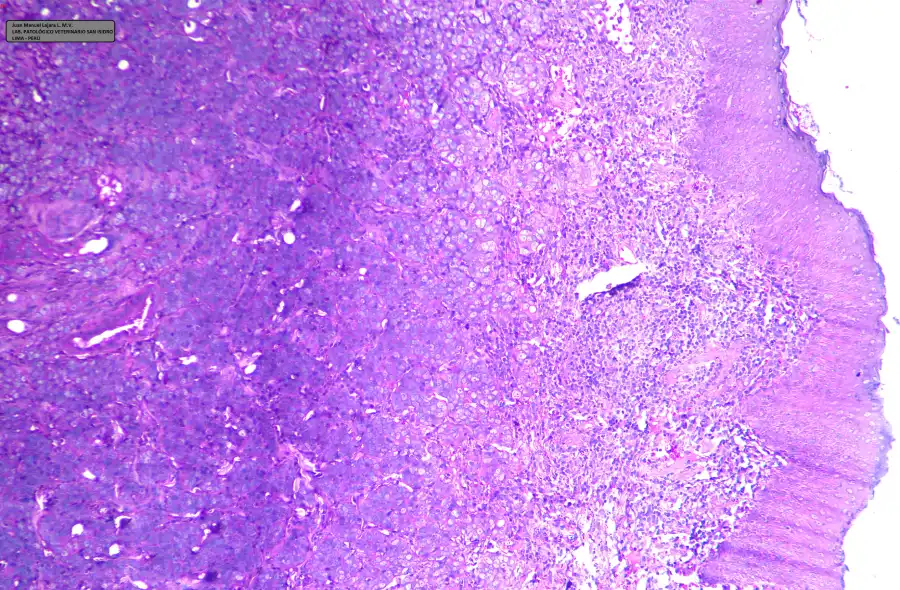

Las muestras para estudio histopatológico fueron coloreadas inicialmente con H-E (Hematoxilina – Eosina) y observadas al microscopio en múltiples aumentos. El resultado histopatológico produjo una inversión en los diferenciales previamente obtenidos por citología con los siguientes resultados:

- 1. ADENOCARCINOMA MAMARIO SÓLIDO Grado III (Alto Grado)

- 2. CARCINOMA DE CÉLULAS ESCAMOSAS (débil)

- 3. MASTOCITOMA (Muy débil)